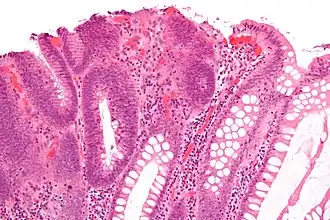

| Villous adenoma | 15%[16] to 40%[15] | Over 75% villous[14] |

| |

The villous subdivision is associated with the highest malignant potential because they generally have the largest surface area. (This is because the villi are projections into the lumen and hence have a bigger surface area.) However, villous adenomas are no more likely than tubular or tubulovillous adenomas to become cancerous if their sizes are all the same.[18]

- Villous adenoma: 40% risk of cancer

Micrograph of a villous adenoma. These polyps are considered to have a high risk of malignant transformation. H&E stain. -